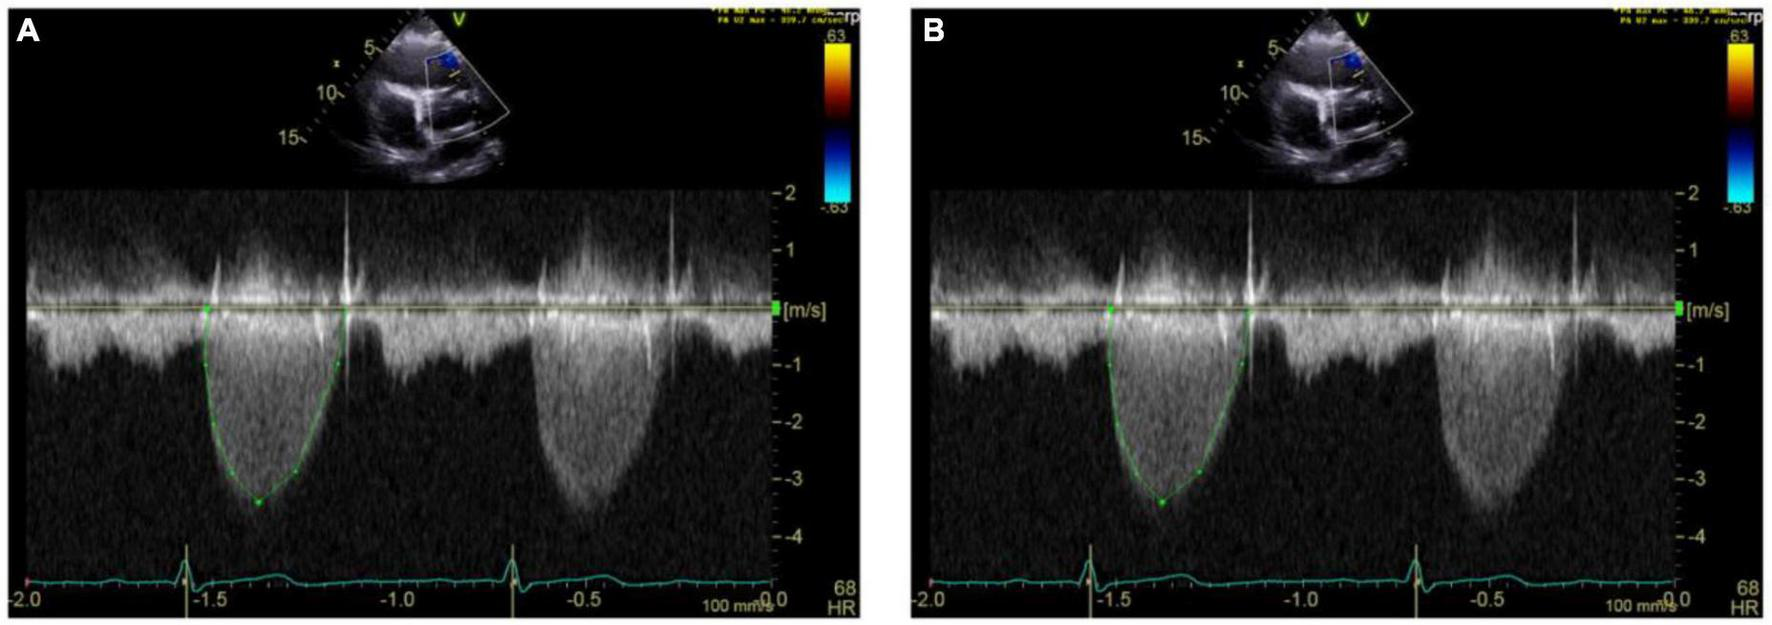

Systematic echocardiographic monitoring played a major role in the post-surgical period. Echocardiography helped us identify the rather-unpredictable timing of the bioprosthetic valve degeneration (Figures 6–8). Pulmonary valve stenosis was the primary indicator of overall degeneration (determined by slight increases in PV velocities, Vmax values, and the severity of valvular regurgitation) and occurred from 6 to 9 months to 2 years after surgery. One patient had a stepwise deterioration that required escalating her treatment regimen from telotristat ethyl treatment to PRRT treatment to achieve valve stabilization.

FIGURE 8

Echocardiography monitoring in carcinoid heart disease (CnHD). Second and third follow up echos. Follow up echo at 6 (A) and 9 (B) months after surgery showing higher pulmonary valve velocities.